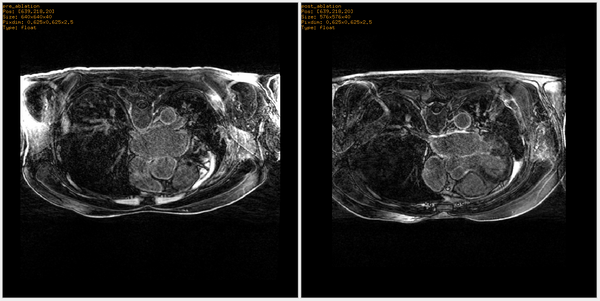

• Example experiment conducted on heart MRI of a patient before and after ablation surgery.

Left) Pre ablation. Right) Post ablation.